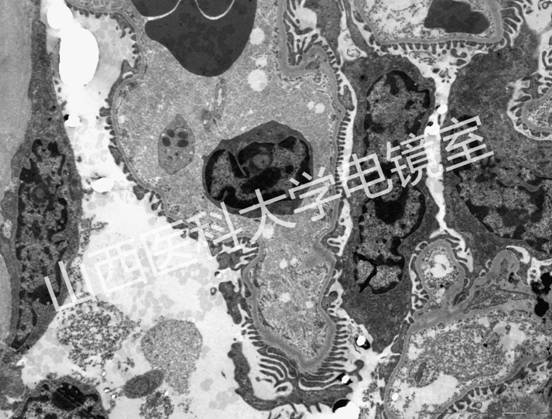

代表性圖譜:

破骨細胞

腎

心肌

心肌閏盤

胰腺內分泌細胞

腫瘤細胞

精子

膠原纖維

細菌

材料